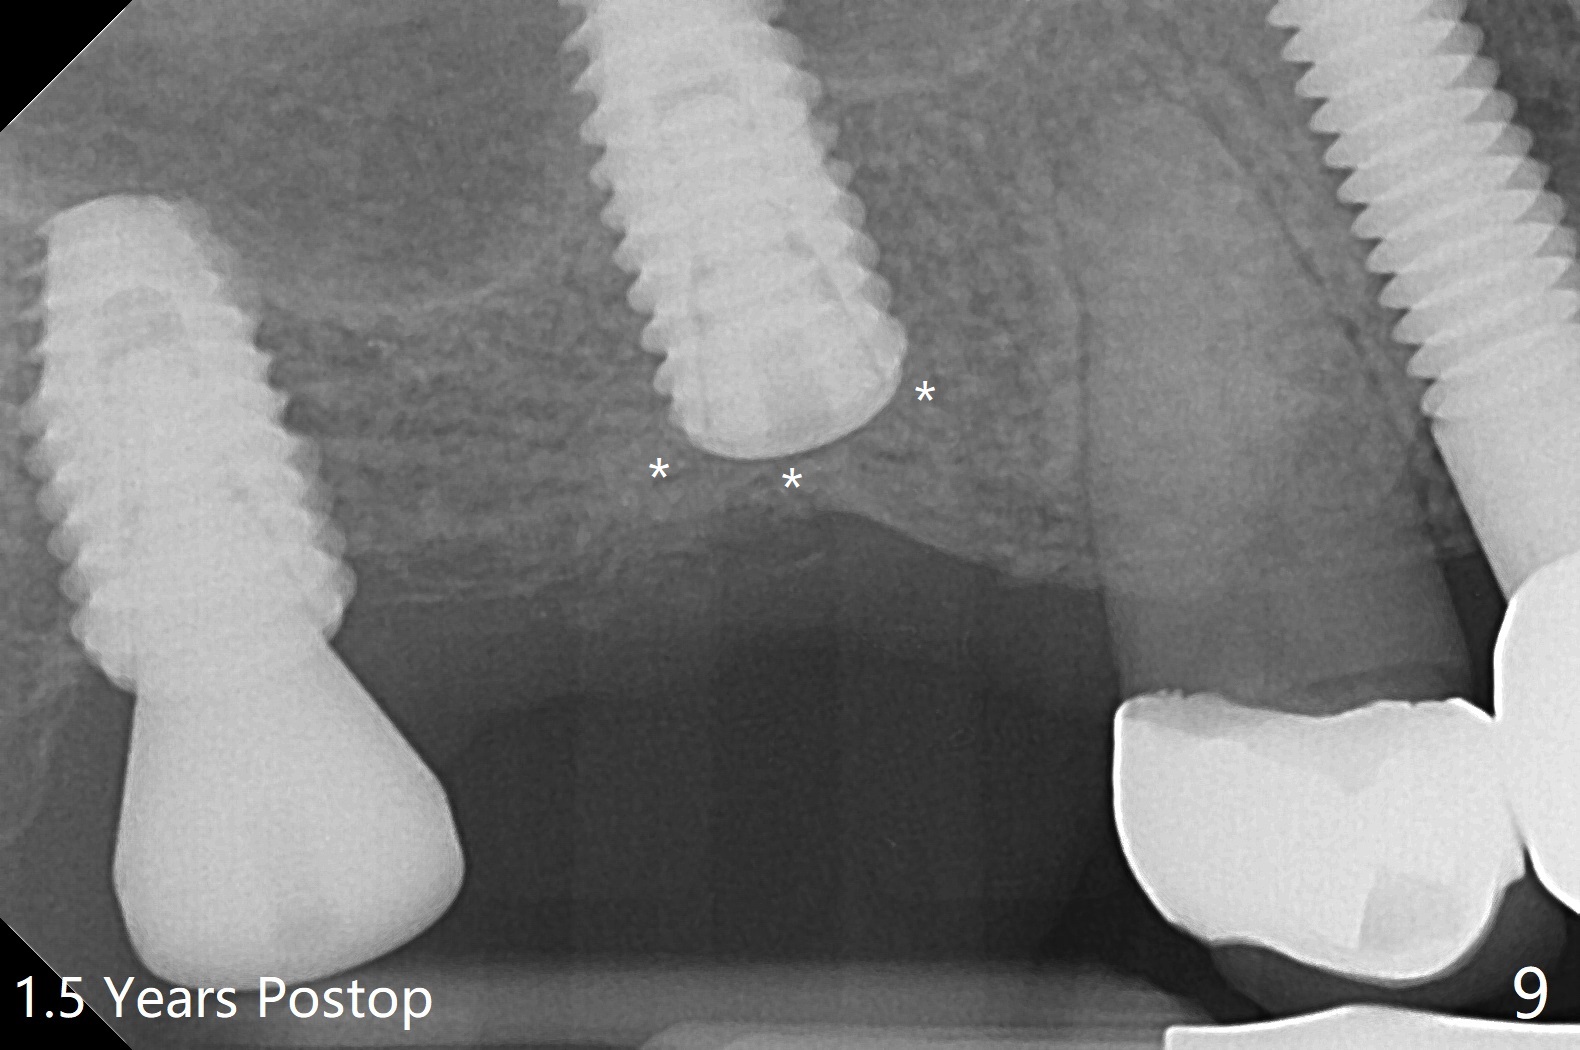

Osteotomy at the sites of #2 and 3 goes on as planned. Sinus lift using DIO 2.8 mm round bur with 6 and 7 mm stoppers (respectively) is carried on without certainty, because it is difficult to feel the stop through the osteotomy. The crest may be uneven or soft. It appears that the soft tissue landmark as a stop may be easier to identify. In fact a 3 mm IBS Magic Expander (an osteotome) was used for sinus lift at #3. The 2 implants are placed with 20 and 30 Ncm (Fig.1,2). Healing abutments are inserted. At 2-week follow-up, the patient reports "pain a few days earlier, took a pill of antibiotic, pain gone. UR metal is sharp". She does not take antibiotic regularly. Exam reveals that there is heavy plaque around #2,3 healing abutments. The buccal edge of #2 abutment is trimmed for comfort. Nearly 1 month postop, #3 healing abutment dislodges with buccal gingival erythema and edema with purulent discharge (Fig.3). Healing screw is placed at #3 with Amoxicillin and Chlorhexidine prescribed. One week later, the implant at #3 turns when the healing screw is retightened (Fig.4). After debridement, Vanilla graft is placed. There is no infection at #2 or 3 four months postop (Fig.5,6); the lingual gingiva is erythematous and edematous at #29 with mobility II (Fig.7 (vertical root fracture)). Uncover is conducted at the site of #3; there is no infection superficial 7.5 months postop (Fig.8). There is a large buccal defect upon incision with dark hemorrhage. In fact the bone density is low crestally (Fig.8 *). Bone graft is placed for the 2nd time. Eleven months later (1.5 years post implant placement), the bone regrows crestal (Fig.9 *). The crown at #3 is loose 1 year 5 months post cementation (Fig.10). After proximal trimming (Fig.11 *), the abutment at #3 is seated completely. After lab repair, crown oral cement, crown/abutment removal for excess cement removal, the crown/abutment cannot be torqued >25 Ncm (Fig.12, 30 Ncm). PA shows incomplete seating (Fig.12 <). Then the crown is sectioned so that the abutment has more freedom to be seated completely with pressure against the gingiva (the patient feels pain, Fig.13). Torque is 30 Ncm. After crown cementation, the abutment will not be removed for cement removal.